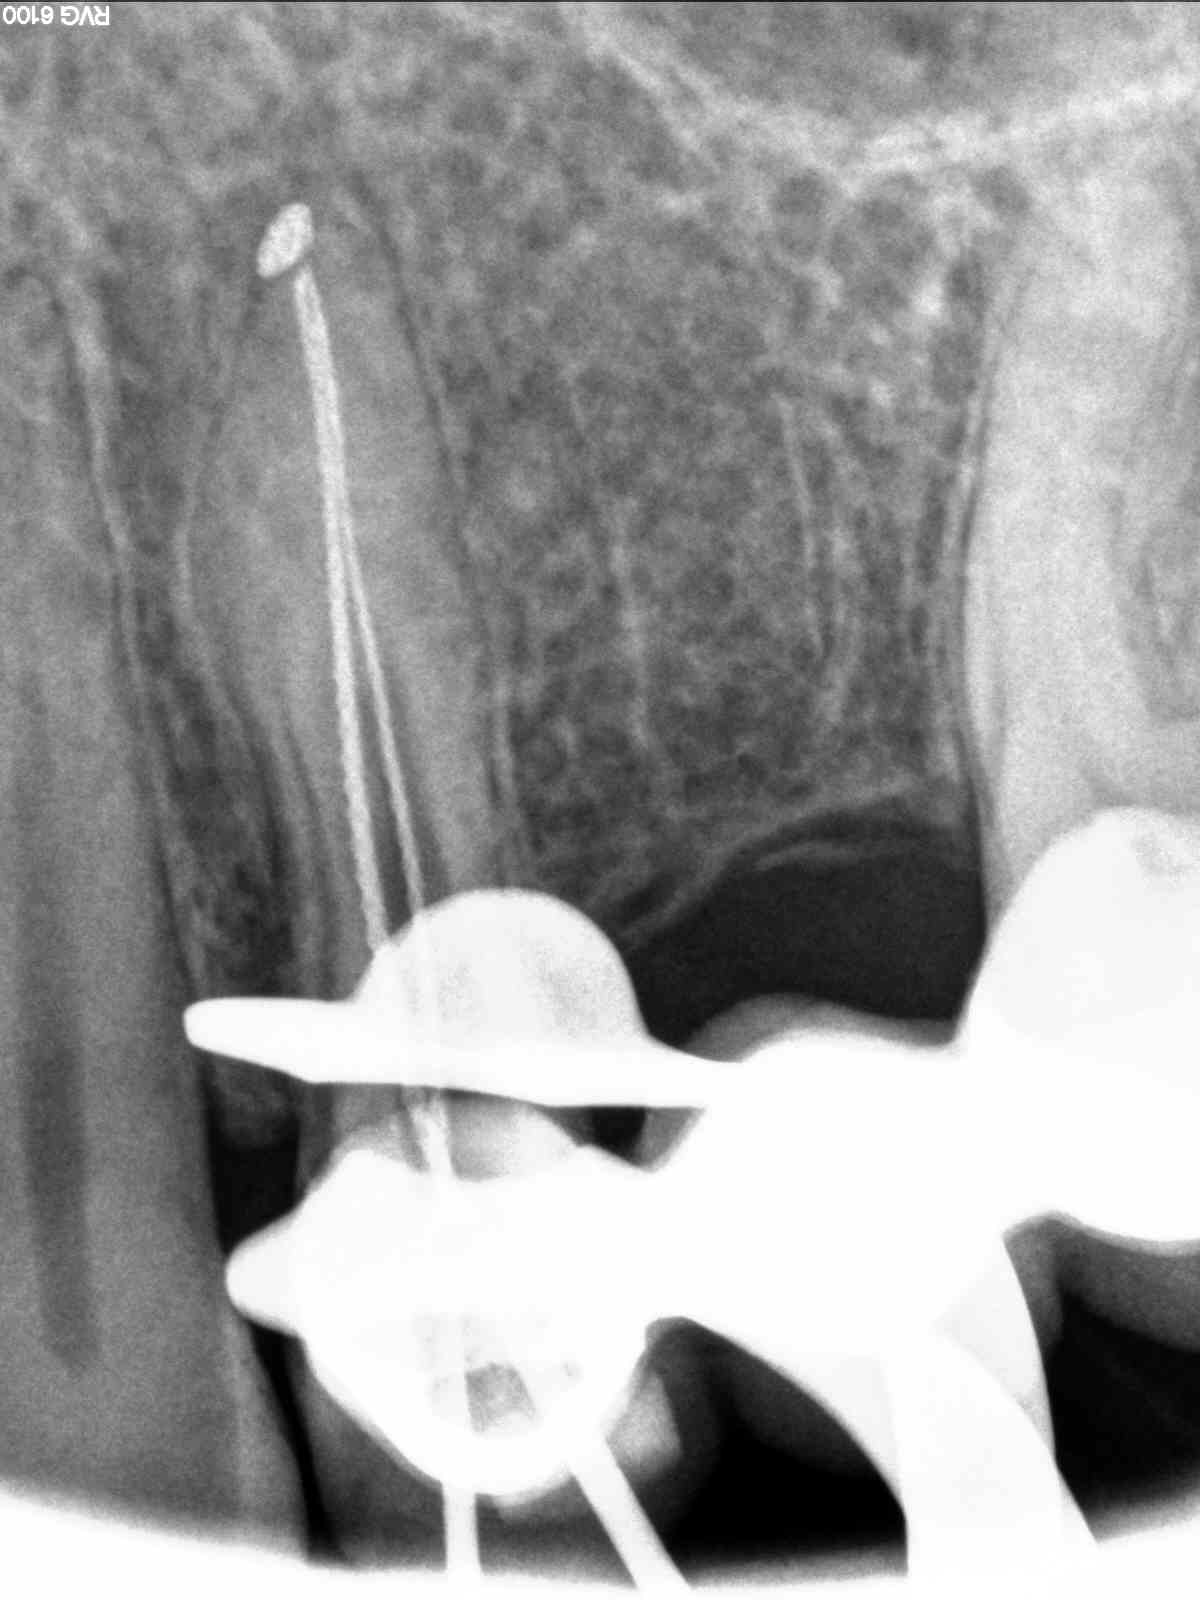

| CaOH with #30 in canal to length. Prior to seeing this I thought I had a pretty standard 1-2-1, but upon seeing this worried i had a 1-2-1-2. |